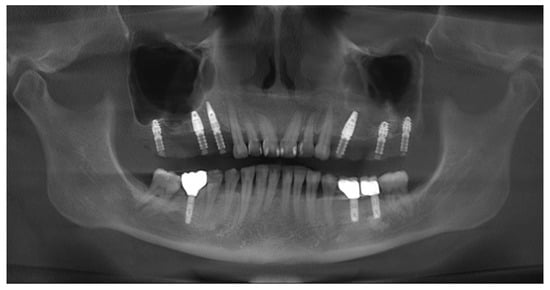

3.1. Case No. 1

3.2. Case No. 2